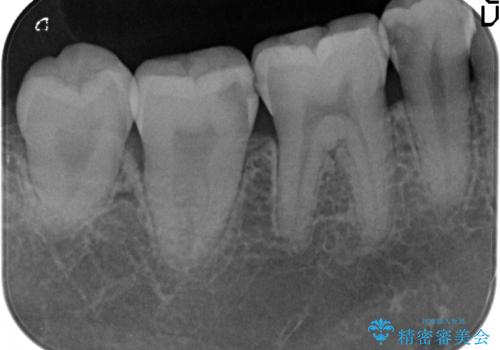

- 右下の奥歯がしみるので診て欲しいといらっしゃった方の症例です。

右下5は虫歯が大きかったため、虫歯を除去後、オールセラミッククラウンによる補綴を行いました。

右下6、7は虫歯を除去後、セラミックインレーによる修復を行いました。